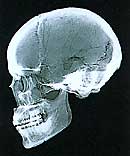

顔の骨では、噛むための筋肉(咀嚼筋)の力が強く加わる部分は、緻密質が厚くなり、海綿質にも太い針状の骨梁が発達し、頑丈な構造になっている。縄文時代人と生きている現代人のレントゲン写真を比べると、骨の構造は縄文人の方がはるかに頑丈なことがわかる。たとえば、前から見ると、下顎骨の下縁の緻密質は縄文人の方が厚く、文字通り緻密である。横から見ると、縄文人では上顎骨の前歯(切歯)の植わっている歯槽骨が上後方に向かって厚く三角形に広がっているが、現代人ではその部分の歯槽骨が薄く湾曲している。現代人では、硬い食物を咬み切ろうとしたら、歯槽骨が折れてしまいそうだ。

一般に、咀嚼筋が発達すると顔が広くなる傾向がある。昔の人々は、硬い食物を食べていたので、顔が広く骨も厚く頑丈だった。しかし、時代が進むにつれ徐々に軟らかい食物を食べることが多くなったので、顔が細長くなり、骨も薄く弱くなった。

縄文人の顔は縦と横が同じくらいの四角で立体的なキリッとした顔立ちである。歯の咬み合わせも毛抜き状であり、硬い干肉でも簡単に咬み切れただろう。古墳時代人の顔もかなり幅広で丸四角であり、エラが張っている人も多い。しかし、咬み合わせは鋏状で、あまりよく咬み切れなかっただろう。米を食べ始めた影響が現れている。江戸時代人の顔はやや細長くなっており、長円というところ。歯槽骨が後退して出っ歯(反っ歯)が目立ち、うまく咬み切れなかったはずだ。

縄文時代人男性

(標本・国立科学博物館/撮影・神奈川歯科大学放射線科)

古墳時代人男性

江戸時代人男性

江戸時代人女性(華奢な庶民)

(標本・国立科学博物館/撮影・神奈川歯科大学放射線科) |